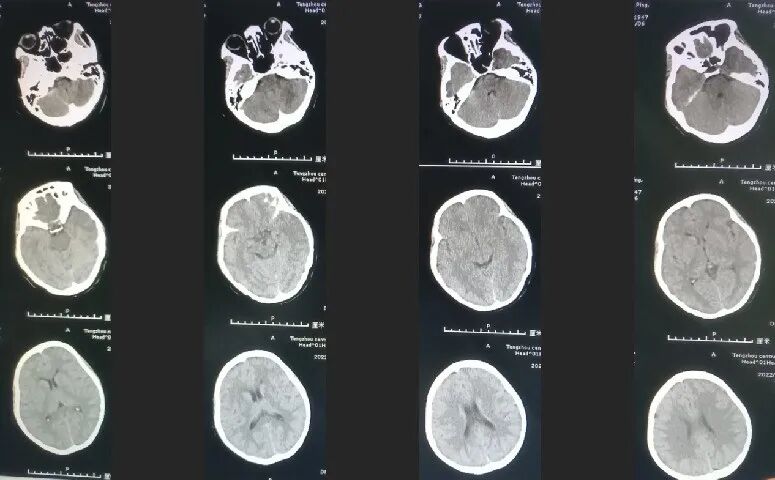

术后影像及检查

导丝怎么扩【载药时代 球扩天下】NOVA DES®颅内药物洗脱支架在颈内动脉颅内段重度狭窄的应用两例!滕州市中心医院&山西医科大学第二医院_https://www.jmylbn.com_新闻资讯_第9张

影像结论:狭窄解除,下干血流通畅。

术后第二天磁共振。

导丝怎么扩【载药时代 球扩天下】NOVA DES®颅内药物洗脱支架在颈内动脉颅内段重度狭窄的应用两例!滕州市中心医院&山西医科大学第二医院_https://www.jmylbn.com_新闻资讯_第10张

术后第二天。

导丝怎么扩【载药时代 球扩天下】NOVA DES®颅内药物洗脱支架在颈内动脉颅内段重度狭窄的应用两例!滕州市中心医院&山西医科大学第二医院_https://www.jmylbn.com_新闻资讯_第11张